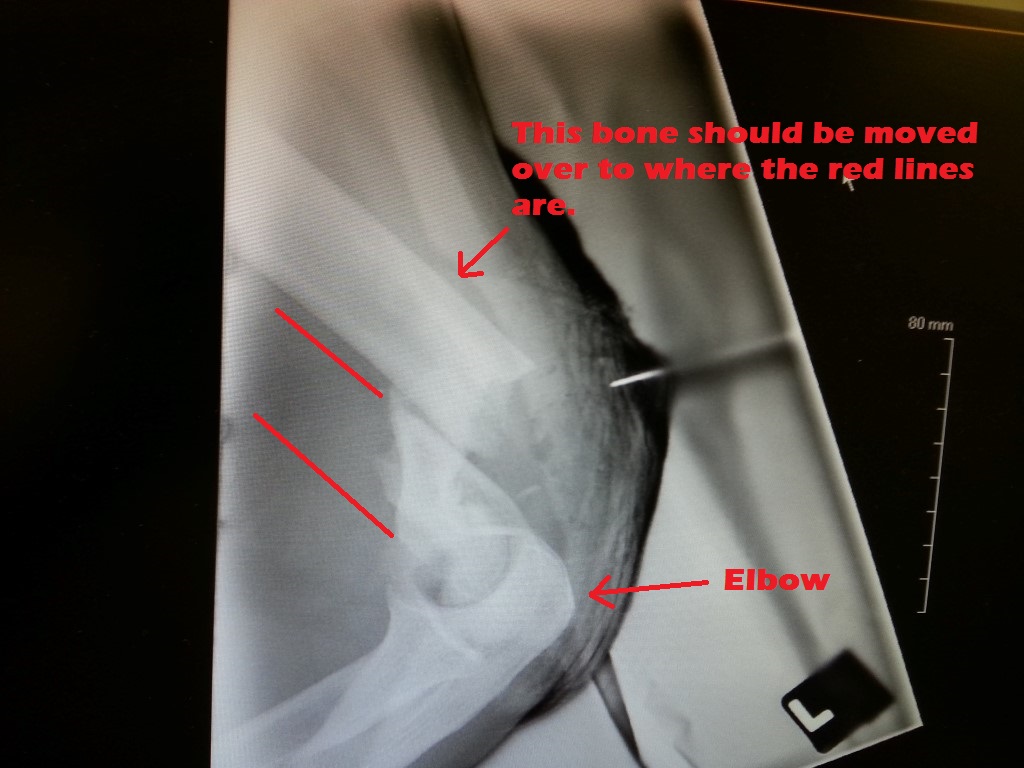

The surgeons notes say: “Left distal humerus fracture. Highly comminuted. Open fracture.”

This means the elbow end (distal) of my left upper arm bone (humerus) was badly shattered (highly comminuted) and bone was exposed thru the skin (open fracture).